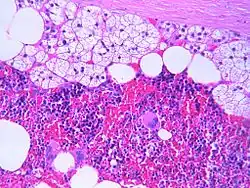

Microscopic features

The microscopic view of a myelolipoma shows the presence of normal adrenal cells, fat (adipose) cells, and the three lineages of the myeloid precursors

The typical microscopic features of myelolipomas are shown in the image. There is a mixture of normal adrenal tissue, fat, and a full trilineage maturation of the three major blood-forming elements: myeloid (white blood cell forming), erythroid (red blood cell forming), and megakaryocytic (platelet forming) lines.[1]